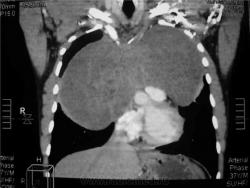

Мужчина 36 лет, рентгеногафия и КТ грудной полости.

Жалобы на субфебрильную температуру, боли в грудной клетке справа, слабость, похудание. ФГ 10 месяцев назад - норма.

КТ август 2009.

КТ контроль октябрь 2009

Интенсивное, однородное затемнение в средних отделах справа, слева норма - мною был заподозрен м/долевой плеврит, пациент был направлен в областной центр торакальной хирургии. Затем онкодиспансер, затем институт рака в Киеве. Результат гистологии тератобластома средостения. 2 курса химиотерапии контрольное КТ в октябре - отрицательная динамика.

Массивное неоднородное мягкотканное новообразование, исходящее из верхней или средней трети переднего средостения, оттесняет крупные сосуды вправо и кзади. По локализации должна быть злокачественная тимома. Хотя и лимфому наверное, не стоит отбрасывать, Ходжкинская маловероятна.